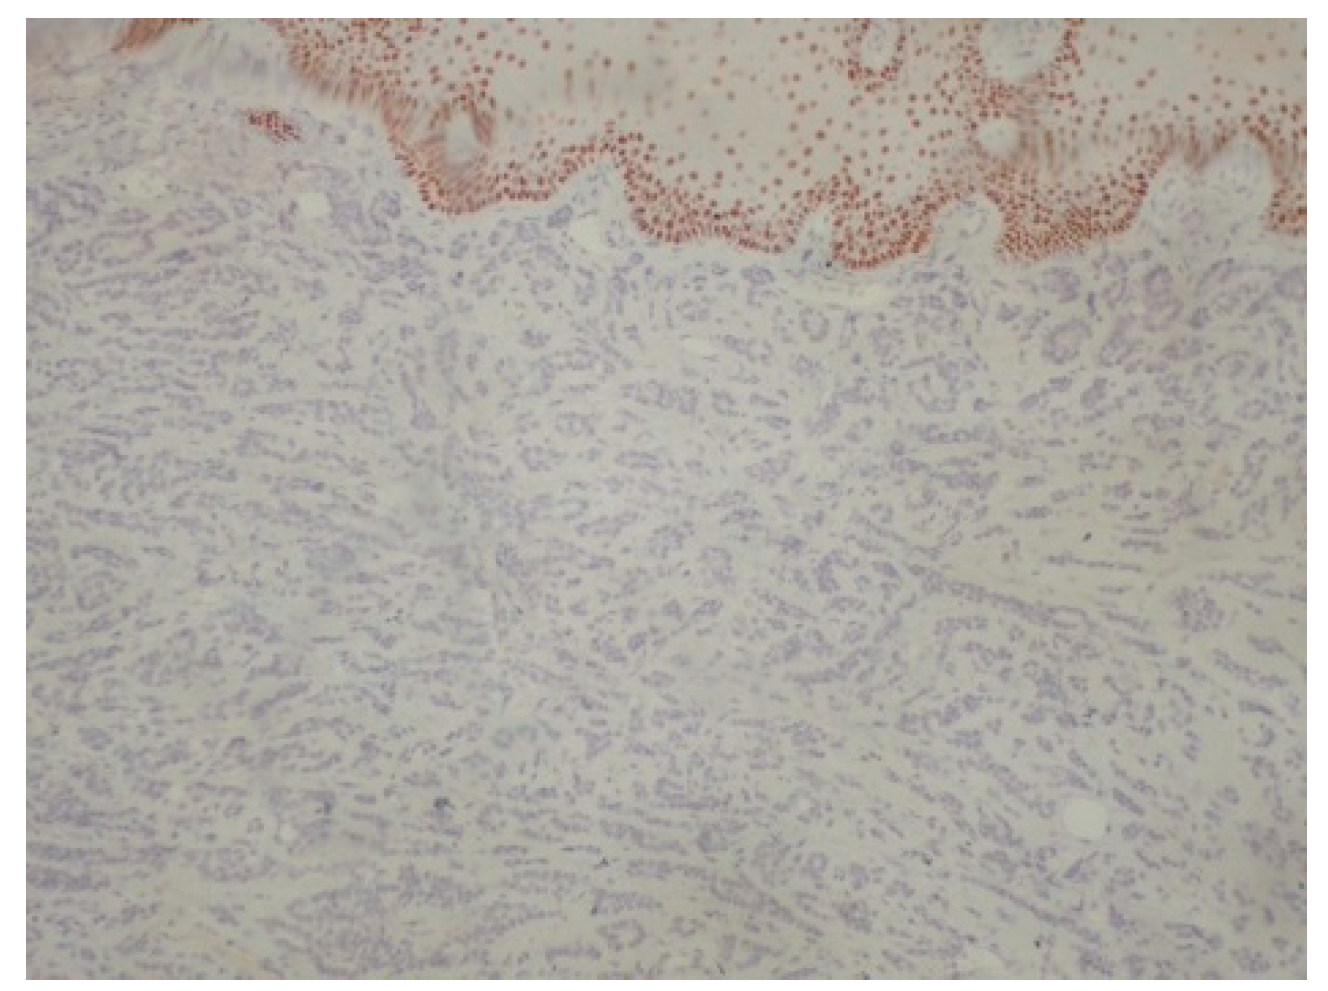

Figure 8.

Negativity of neoplastic cells for p40. p63+/p40− immunophenotype is important diagnostic clue for polymorphous adenocarcinoma (immunoperoxidase ×100).

Successfully diagnosing oral polymorphous adenocarcinoma requires specific immunohistochemical markers. One such marker, p63, is frequently positive, and studies have indicated a 100% positivity rate; however, p63 also shows frequent positivity in both adenoid cystic carcinomas and pleomorphic adenomas [3]. p40 immunostaining emerges as a crucial tool, as it is effective in distinguishing polymorphous adenocarcinoma from adenoid cystic carcinomas and pleomorphic adenomas, with all polymorphous adenocarcinoma cases in the study showing negative results for p40 (as in our case) [3]. Furthermore, uniformly positive vimentin and cytokeratin 7 (as in our case) staining can also suffice for a final diagnosis, albeit these markers may not be informative in cases involving rare two-layer ducts [4]. Estrogen receptors are also expected to be negative in pleomorphic adenomas, Warthin’s tumors, mucoepidermoid carcinomas and adenoid cystic carcinomas [5,6]. The expression of hormone receptors in salivary malignancies may vary [7], and one study also shows negative results regarding the presence of estrogen receptors in polymorphous adenocarcinoma [8]. This may be interpreted as follows: estrogen receptors do not belong to the strict immunophenotype of polymorphous adenocarcinoma; however, when positive, screening and imaging of the breast should take place. In our case, the mother of our patient had a medical history of breast cancer, and due to this association between breast cancer and salivary gland cancer [8], the patient was advised to consult a gynecologist. A detailed examination of histological features enables the accurate identification of tumor type, stage, and grade. Diagnosing oral polymorphous adenocarcinoma, especially from adenoid cystic carcinoma, is important, as the management strategies for these tumors differ significantly [9]. Adenoid cystic carcinoma often requires more aggressive treatment approaches like radical neck dissection and adjuvant radiotherapy, which are not typically necessary for oral polymorphous adenocarcinoma [9]. In the case of limited biopsy material, due to the localization in cases such as ours, the oral and maxillofacial pathologists may struggle to obtain sufficient tissue to make a definitive diagnosis [9]. Furthermore, the tissue specimen should be taken from the center of the lesion to depict accurately the histological characteristics of the palatal tumors such as salivary gland neoplasms and lymphomas. Surgical excision with clear margins remains the cornerstone of management of the disease, aiming to reduce the risk of local recurrence, rarely even decades post-diagnosis, or the risk of uncontrolled metastases, which may take place much later than initially expected [10,11]. The guidelines recommend follow-up lasting 10 years or more for effective management of the disease [12]. Radiation therapy may be considered as an adjunct to surgery, particularly if surgical margins are positive or if the tumor localization does not allow for its complete surgical resection [13]. This approach depends also on the tumor’s histopathological complexity, since it may complicate diagnosis, and necessitate aggressive initial treatment [14]. Factors such as tumor size, depth of invasion, and extent of lymph node involvement significantly influence the surgical approach [15]. A recent retrospective study of minor salivary gland tumors reported polymorphous adenocarcinoma as the most common entity (12/30 patients). Most of the patients manifested well-differentiated tumors. A total of 29/30 patients were treated through surgery, 11/30 received adjuvant radiotherapy, and 6/30 received chemotherapy. The relatively high recurrence rate of 26.66% was registered [16]. In our case, the prompt biopsy and definitive surgical treatment elevates the possibility of avoiding any recurrence, and ensuring that the patient will enjoy a disease-free future. This case further illustrates the importance of immunohistochemistry and the need to biopsy even benign-appearing lesions.